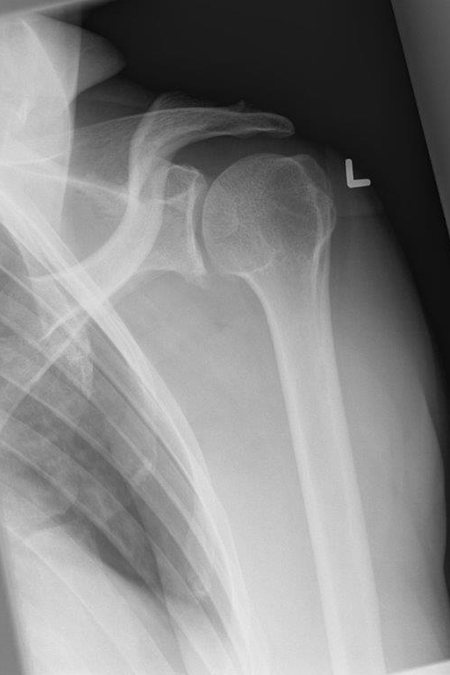

65-jährige Patientin mit Schulterluxationsverletzung und intraoperativ sehr kleinteiliger Bruch des vorderen Pfannenrandes. Auf der Gegenseite erfolgten vor ein paar Jahren mehrere operative Eingriffe initial mit bleibender Instabilität und letztendlich einer Drehosteotomie am Oberarm zur Stabilisation des Gelenkes. Die Patientin wünschte jetzt eine Stabilisationsbehandlung mit bestmöglicher Sicherheit. Wir führten eine Versetzung des knöchernen Rabenschnabelfortsatzes an den unteren Pfannenrand durch (Latarjet-Operation). Durch den Schlingeneffekt der mitversetzten Sehne des kurzen Bizepskopfes kommt es zu einem doppelten Stabilisationseffekt. Der Patientin konnte eine sehr stabile Gelenksituation geschaffen werden bei guter Funktion.

SCHULTERINSTABILITÄT MIT PFANNENFRAKTUR – LATARJET-STABILISATION

Bild Latarjet Stabilisation